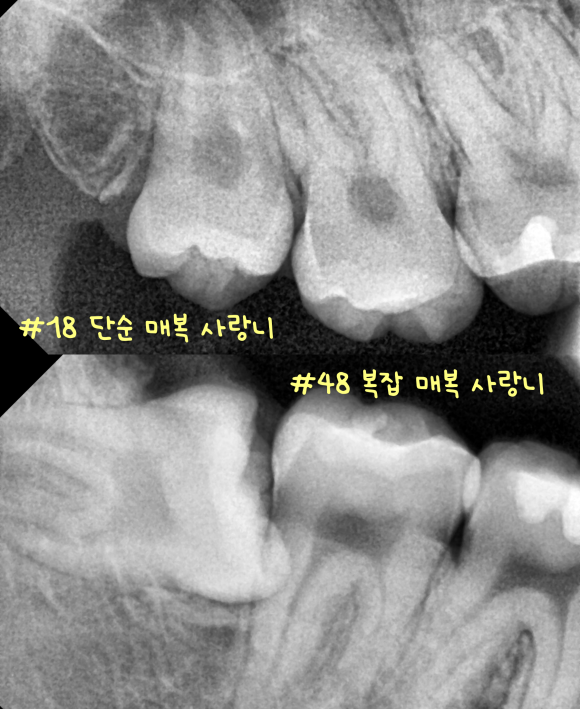

촬영일 : 250728

예시 사진처럼 사랑니가 모두 매복인 경우도 있고

올곧게 자란 분들도 계시는데요.

누워 있는지, 뿌리가 갈라졌는지, 신경과 얼마나 가까운지,

그리고 염증이 반복되고 있는지에 따라 난이도는 크게 달라집니다.

묻혀 있는 매복은 분할 발치를 통해

잇몸 절개를 줄여드리고 있습니다.